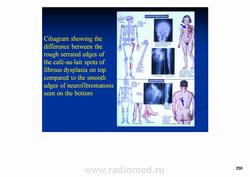

Фиброзная дисплазия — заболевание, характеризующееся нарушением развития (дисплазия) скелета, при котором нормальная кость замещается фиброзной тканью с элементами диспластически изменённой кости. Выделяют монооссальную (около 85% случаев), мономелическую (поражено несколько соседних костей одной конечности, плечевого или тазового пояса) и полиоссальную (около 5% случаев) формы. Фиброзная дисплазия как аномалия развития иногда сочетается с внескелетными расстройствами: 1) полиоссальная форма поражения сочетается с преждевременным половым созреванием и пигментными пятнами на коже в виде кофейных пятен (Albright’s syndrome); 2) сочетание фиброзной дисплазии с миксомами мягких тканей (Mazabraud’s syndrome). Встречается в любом возрасте, наиболее часто в первые 3 десятилетия жизни (70% больных). Монооссальная форма несколько чаще встречается у лиц мужского пола, при полиоссальной форме соотношение лиц мужского и женского пола 2 : 1. Поражается любая кость, наиболее частая локализация: проксимальная часть бедренной кости, большеберцовая и плечевая кости, рёбра, кости черепа, шейного отдела позвоночника. Поражение костей позвоночника только в 2,5% случаев.